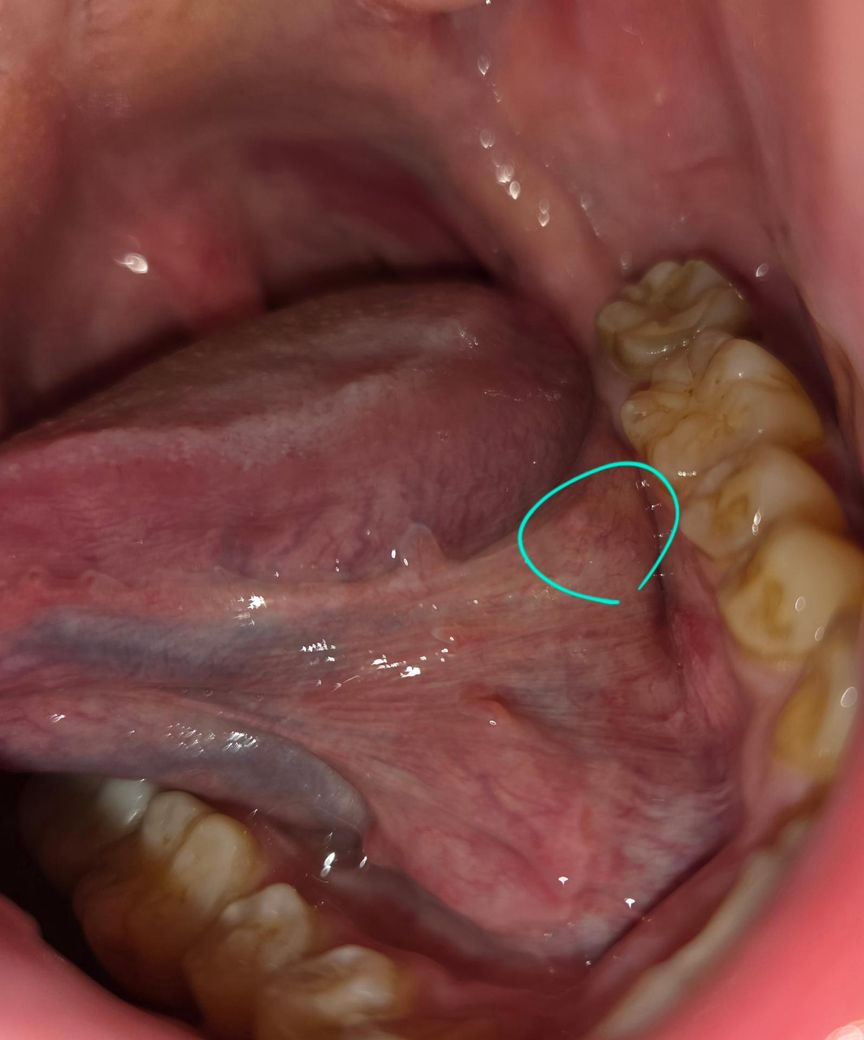

혀 왼쪽의 아래 부분에 어떤 여드름 같은 게 나서 문제가 될지, 문제가 된다면 저게 무엇인지 궁금합니다.

불편한 점이 있어서 확인을 하신 걸까요? 특별한 증상은 없고, 병변 자체도 이상이 있어 보이지는 않거든요. 치아 상태만 보면 흡연자일 것 같고, 구강암을 염려하시는 것 아닐까 싶은데 암으로 보이지는 않습니다. 그래도 금연은 하시는 것이 좋겠지요.